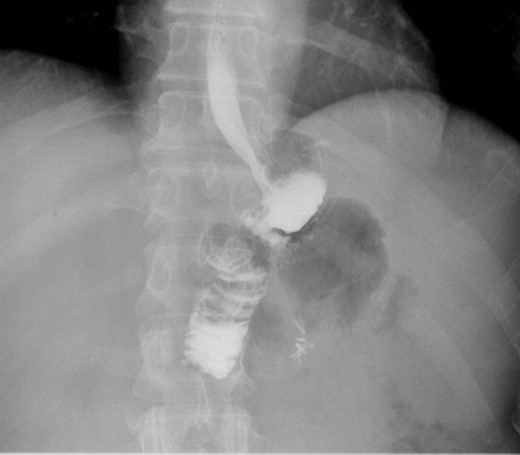

Second patient is a 35-year-old female with BMI 32.3 of with history of diabetes mellitus, hyperlipidemia who underwent LRYGB in June 2014, laparoscopic cholecystectomy 2014 was seen in the clinic for 1 year follow up. After having lost 54 pounds with right sided abdominal pain associated with nausea and vomiting. Patient had an upper GI which was negative and subsequently still continue to have the abdominal pain and undergone an EGD which was normal as well. At that point patient was lost to follow up for over a year as she moved to Florida and states while in Florida had CT scan of abdomen which showed questionable internal hernia at the anastomosis. Patient was seen and evaluated in our emergency room with complaints of right sided abdominal pain with nausea and vomiting. Vital signs were stable. On physical exam, tenderness in the epigastric area. All the labs findings were unremarkable. CT scan of abdomen did not show any abnormality. However, due to possibility for an internal hernia, patient was admitted and was taken to the operating room for diagnostic laparoscopy on November 2017. She was found to have long candy cane limb. We resected excessive redundant 4 cm length of the long blind jejunal loop of gastrojejunostomy anastomosis using Endo GIA Tri-Stapler device, Intra-op EGD was performed showing 4 cm gastric pouch. Post-operative course was uneventful. The patient was discharged to home on post-operative Day 4 and returned to clinic 1 week for follow up and tolerating diet and completely asymptomatic and pain free. Three weeks post laparoscopy patient had upper GI which was found to be normal (Figs 3 and 4).